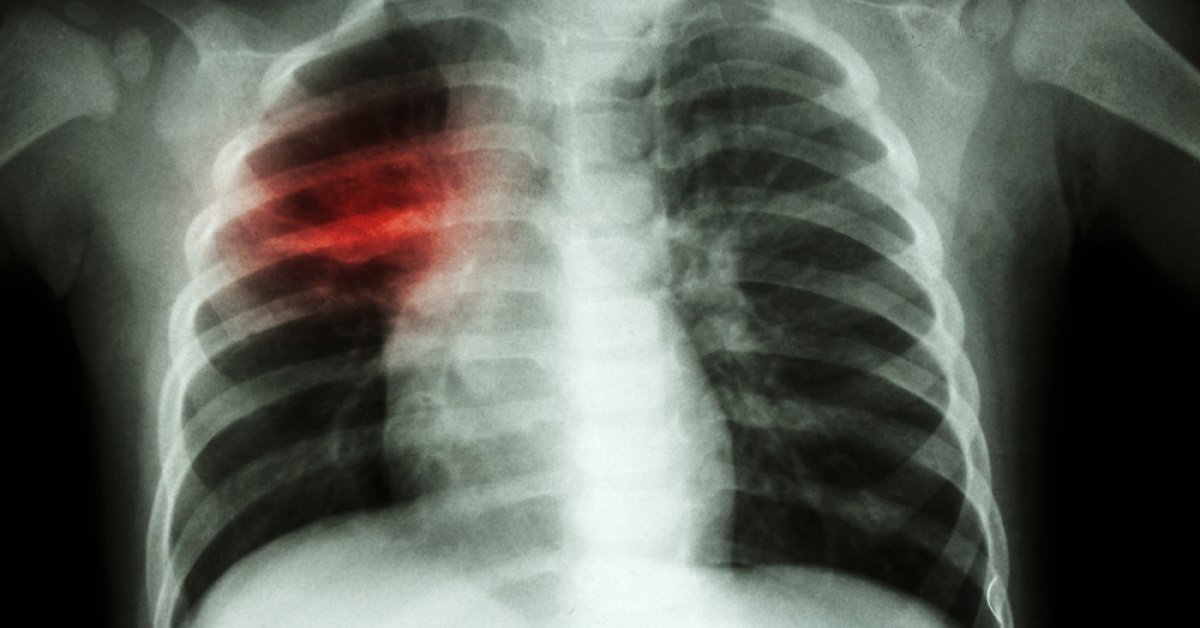

Göğüs Hastalıkları Uzmanı Prof. Dr. Tevfik Özlü, en sık görülen tablonun zatürre olduğuna dikkat çekerek, “Şu anda en sık hastaneye yatış nedenleri arasında bu grupta görülen zatürre ve mevcut hastalıkların alevlenmesi yer alıyor” dedi.

EN SIK GÖRÜLEN TABLO ZATÜRRE

En sık görülen tablonun “zatürre” olduğunu belirten Özlü, “Enfeksiyon akciğere inebiliyor, bazen de bronşit şeklinde karşımıza çıkıyor. Nefes darlığı, hırıltılı solunum, göğüste tıkanma hissi, balgam çıkaramama ve öksürük krizleri görülebiliyor. Gece boyunca süren öksürük hastayı uyutmayabiliyor. Bazı vakalarda yüksek ateş, nefes darlığı ve morarma gibi zatürre belirtileri ortaya çıkabiliyor. Göğüs ağrısı da eşlik edebiliyor. Bunun yanı sıra enfeksiyonlar, kronik hastalıkların alevlenmesine de yol açabiliyor. Örneğin şeker hastalarında kan şekeri birden kontrolden çıkabiliyor. Kronik böbrek hastalığı olanlarda üre ve kreatin değerleri yükselip vücutta ödem ve şişlik oluşabiliyor. KOAH, astım ya da akciğer sertliği gibi hastalığı olanlarda öksürük, balgam ve nefes darlığında belirgin artış görülebiliyor. Kalp yetmezliği bulunan hastalarda ise ödem, nefes darlığı, çarpıntı ve göğüs ağrısı tabloya eklenebiliyor. Bu nedenle viral solunum yolu enfeksiyonlarını özellikle yaşlı ve kronik hastalığı olan kişilerde ciddiye almak gerekiyor. Şu anda en sık hastaneye yatış nedenleri arasında bu grupta görülen zatürre ve mevcut hastalıkların alevlenmesi yer alıyor. Genç ve sağlıklı kişilerde ise tablo genellikle daha hafif seyrediyor. İnfluenza, rinovirüs ve RSV gibi virüsler çoğu zaman ağır bir tabloya yol açmıyor. Genç hastalarda 3-4 gün süren hafif ateş, üşüme ve titreme görülebiliyor, ardından belirtiler gerileyebiliyor. Ancak gençlerde sık karşılaşılan bir durum da uzayan öksürük. Hastalar genellikle ‘Bir hafta, 10 gün ya da bir ay önce grip oldum ama öksürüğüm geçmedi’ şikâyetiyle başvuruyor. Bu durum genellikle hava yolu aşırı duyarlılığına bağlı gelişiyor. Ateş, üşüme, titreme ve halsizlik gibi diğer belirtiler geçmiş olsa da kuru ve inatçı bir öksürük devam edebiliyor. Bunun da ayrı bir tedavi yaklaşımı bulunuyor” şeklinde konuştu.